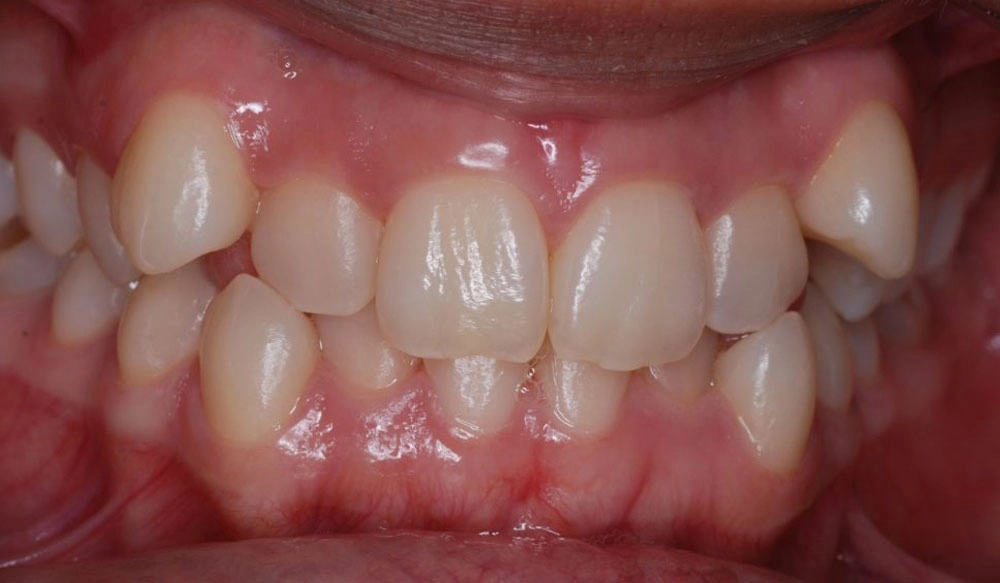

Crowding

Crowding is the condition in which there is a discrepancy between tooth size and space available for the teeth to be aligned in the dental arch

Patient Information:

Age: 17

Gender: female

Invisalign Treatment Option: Invisalign Comprehensive

Total Treatment Time:

29 months